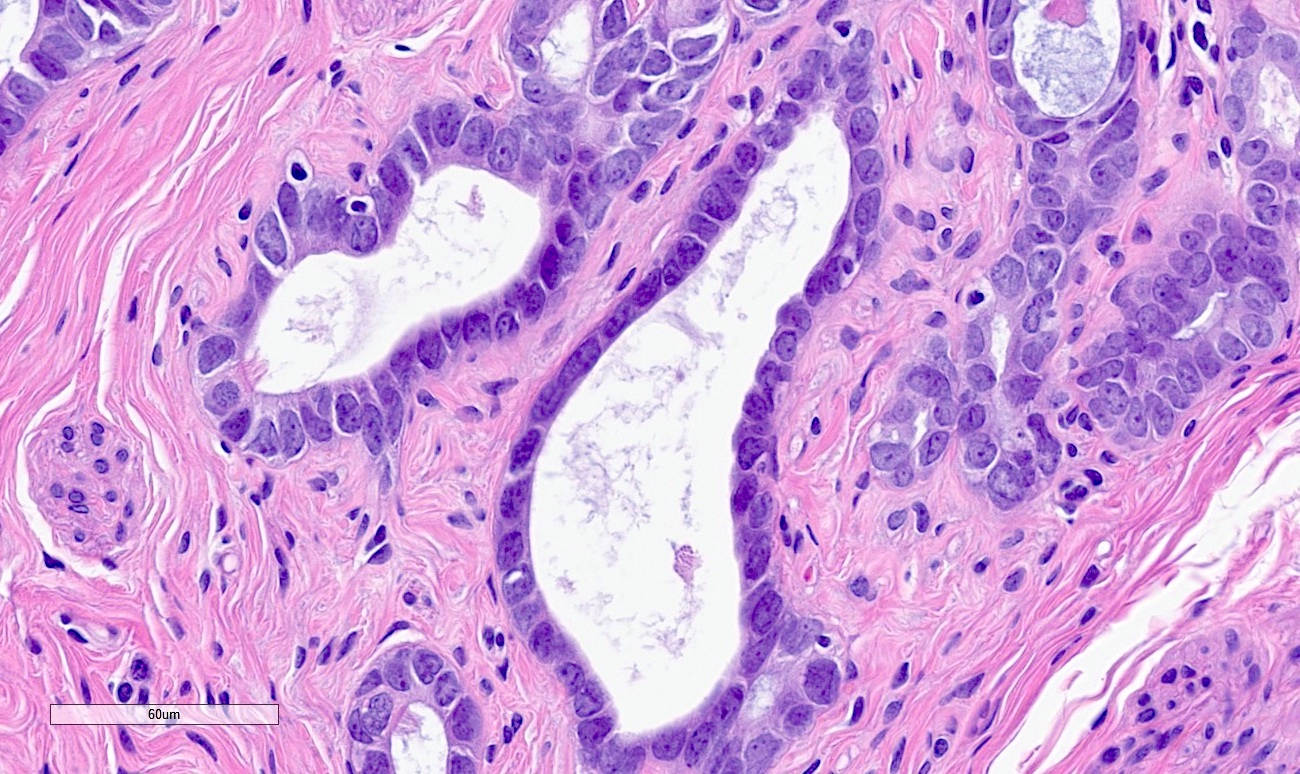

Microscopic (histologic) description

- Regularly spaced glands lined by normal appearing tubal epithelium surrounded by smooth muscle or fibrous tissue

- Tubal lumina are true diverticula that communicate with the central tubal lumen but do not connect with the serosa

- Glands can become cystically dilated (Am J Clin Pathol 1951;21:212)

- No significant atypia, scarring or associated inflammatory / stromal response

- Absence of endometrial stroma differentiates this entity from tubal endometriosis

Microscopic (histologic) images